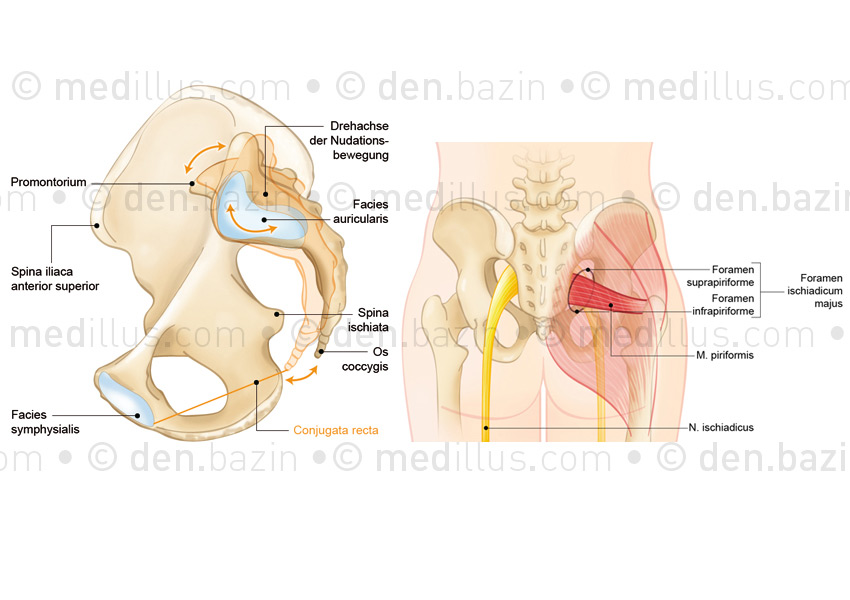

Anatomie du bassin, muscles et nerfs